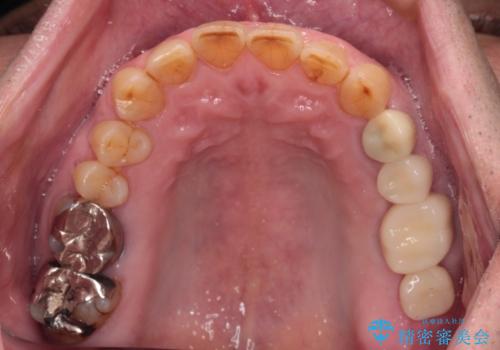

割れてしまった奥歯 インプラントによる補綴治療

- 上下の奥歯が痛いとのことで来院された患者様です。

診察をしたところ、上下大臼歯の歯肉に排膿路認められたため、根管治療を行い、その後補綴治療を行うこととしました。

また、上顎の欠損部位にはインプラント治療を行うこととしました。

治療を開始したところ、上顎は排膿路が消失し、症状も落ち着きましたが、下顎は一向に改善されませんでした。

改めて診療を行ったところ、歯根破折が認められ、抜歯後にインプラント治療を行うこととしました。

下顎大臼歯の抜歯決断までに時間がかかったため、治療期間はやや長くなりましたが、安定した咬み合わせとなり、痛みもなく安心して噛めるようになりました。